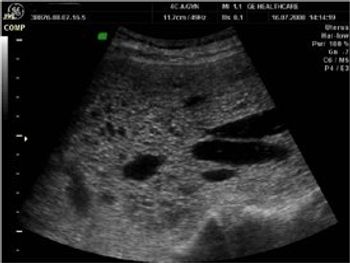

Is this lesion a fibroid or adenomyosis? Patient is a young (38n yr. old) married female with a history of dysmenorrhea and polymenorrhoea.